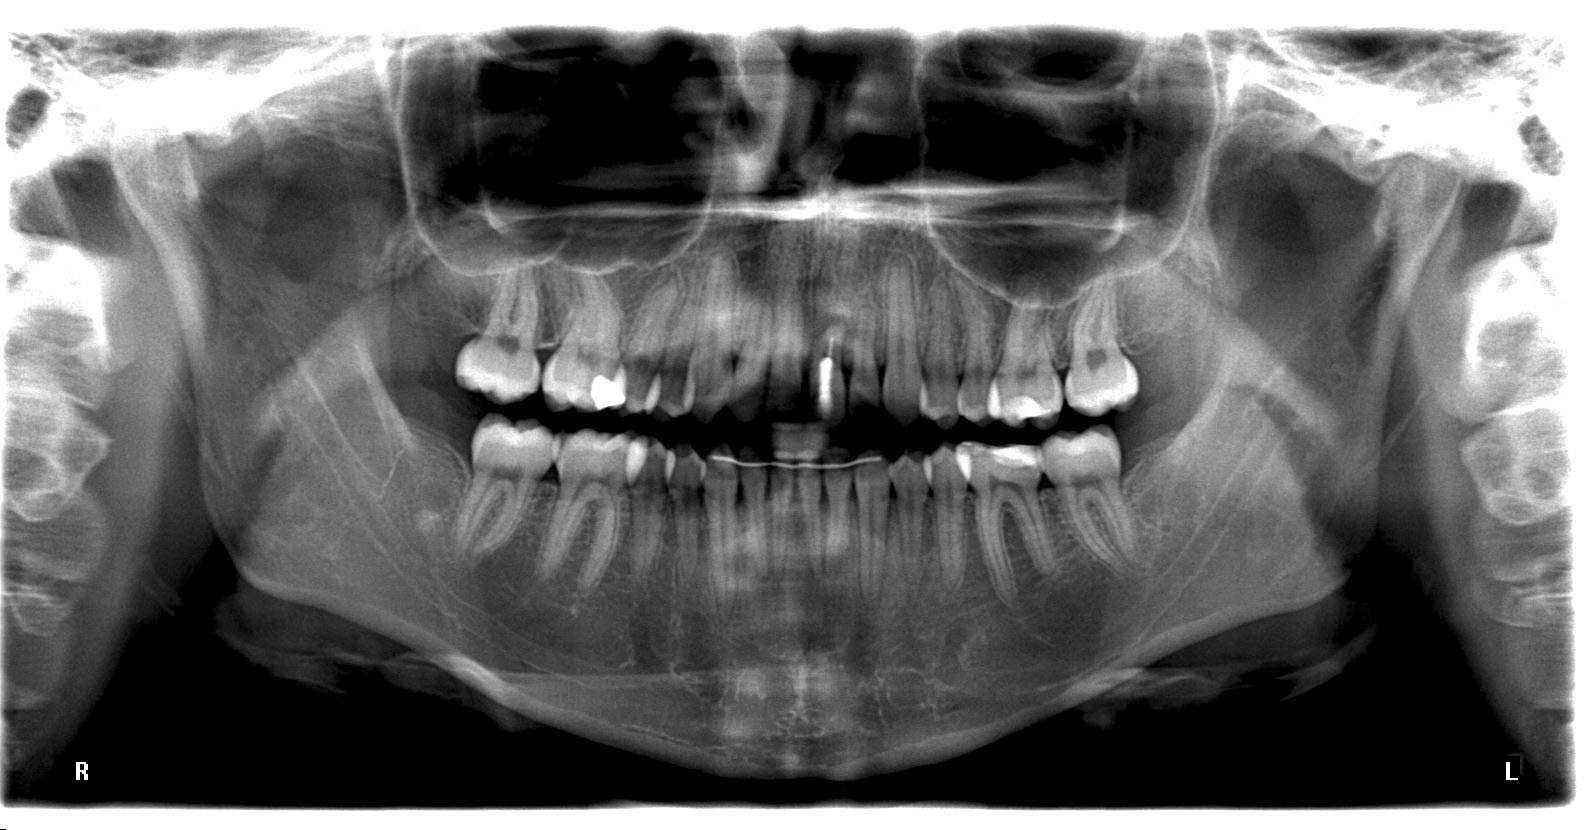

OPG-2

1595 × 830

Hoffnungsloser Frontzahn – Lockerungsgrad 3